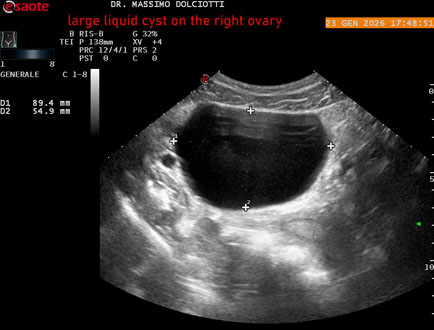

Data inserimento: 26/01/2026

Ecografia del: 23/01/2025

Strumento: Esaote MyLab Eight

Sonda: Conevx Multifrequenza 1-8 MHz

Età Paziente: F 29 anni

Motivazione dell'esame: dolore al lato destro della pelvi in portarice di cisti liquida all'ovaio destro.

Commento all'esame: le immagini ed il video documentano, in sede pelvica, grande formazione anecogena, delle dimensioni di 110 x 60 mm, priva di vascolarizzazione, da ricondurre a grande cisti liquida dell'ovaio destro.

Conclusioni: grande cisti liquida all'ovaio destro (large fluid cyst on the right ovary).

In collaborazione: Dr.ssa Marica Manfredi - Ancona, Dr. Ilir Qose - Ancona

Presentazione: Dr. Massimo Dolciotti - Ancona

Elaborazione digitale: Andrea Dini - Ancona